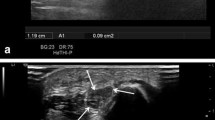

Near-field imaging by the use of higher frequencies and harmonic imaging have greatly contributed to improved joint and tendon surface visibility as compared with the visibility achieved with conventional B-mode US. Harmonic imaging has been found to be superior to conventional US for diagnosis of subscapularis tendon abnormalities [3]. When using spatial compound imaging, electronic US beam steering of a transducer array during real-time acquisition results in improved delineation of lesions, because images are generated from different view angles. This is of special value in assessing structures with specular surface echoes such as tendons, nerves and muscles, because one of the several view angles will be perpendicular to the tissue, generating a higher echo amplitude even at an insonation angle causing anisotropy on conventional B-mode US [2]. Anisotropic artefacts have long been recognised as a problem for MSK imaging since anisotropic structures such as tendons and ligaments, due to their oblique course, are less well depicted (Fig. 1a,b). To overcome anisotropy, instead of manual transducer angulation and tilting, a newer steering-based option, which can be activated by pressing a button on the keyboard, tilts and angulates the US beam in order to steer the whole B-mode image itself. This technique can also help better differentiate insertional tendinosis, where often a part of the fibres run an oblique course causing hypoechoic patterns of uncertain pathological value.